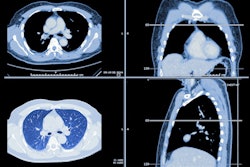

The Worcestershire Royal is one of the facilities operated by the Worcestershire Acute Hospitals NHS Trust. Photo courtesy of Paul Weston/Alamy Stock Photo.A committee looked at 30% of the x-ray backlog at the trust and identified three missed lung cancer cases, as well as another 20 to 30 possible cases of cancer, the BBC reported. If nothing had been done, more than 42,000 x-rays and scans would have gone unexamined by an expert the following year, so a range of options for dealing with the issue were recommended.